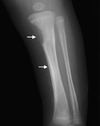

This radiograph, from an infant with congenital syphilis, shows multiple bony changes, including destruction of the medial metaphysis of the left tibia (top white arrow) and diffuse tibial periosteal reaction (bottom white arrow). These findings illustrate Wimberger sign

Figure 3. Radiograph with Wimberger's Sign

Source: reprinted from Stephens JR and Arenth, J.  Wimberger Sign in Congenital Syphilis. J Pediatr. 2015;167:1451. Copyright 2015 (reproduced with permission from Elsevier).